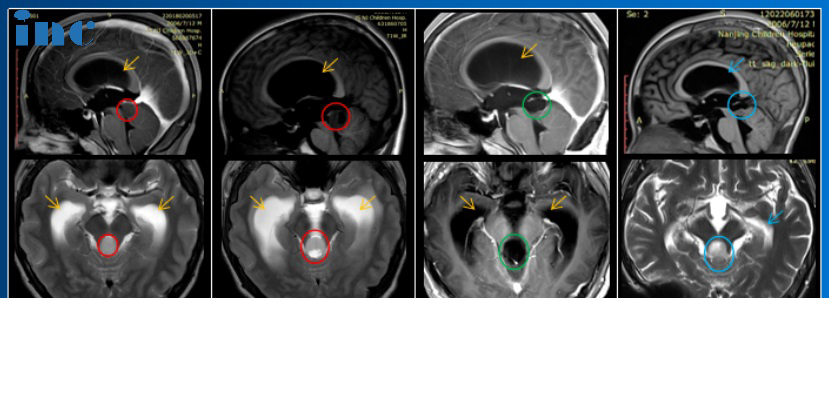

49岁的魏先生2022年8月底出现呕吐、食欲不佳、伴轻度头晕,行脑部CT 提示无异常。然而仅仅过了一个月,行颈椎磁共振,提示延髓占位性病变,怀疑低级别胶质瘤,且核磁片子显示肿瘤部分呈弥漫性生长。肿瘤位置和成长形态都很复杂,手术难度较大,然而不手术,可能面临着肿瘤持续生长压迫到脑干,造成瘫痪、呼吸障碍、甚至死亡等无法想法的后果;另一方面,如果肿瘤不是预期的低级别,那么发展速度更是难以想象。所以尽可能手术切除肿瘤减少肿瘤压迫、手术尽快明确肿瘤病理是目前治疗路上较重要的两个目标。和许多低级别胶质瘤病友选择保守治疗不同的是,魏先生只想尽快找到解决眼前问题的较佳办法。在多方查询下,魏先生找到了INC德国巴特朗菲教授,希望教授能为自己手术。

而巴教授的评估结果也坚定了魏先生选择手术的想法。巴教授:“我认为等待一段时间做手术对并不利于病人,而是有利于肿瘤的进一步生长。”

2022年12月2号,中国疑难示范手术期间,在苏州独墅湖医院,巴教授顺利为魏先生手术,手术切除率达到90%以上,比教授术前评估的70%高出20%多,术后无新发后遗症,术后一天,魏先生手脚可活动、对答如流,术后三天魏先生恢复良好,坐在病床上深深向巴教授三作揖,感激巴教授的救命之恩。

术后一周,与初次诊断“低级别胶质瘤”不同的是,魏先生的病理结果显示为恶性四级弥漫中线胶质瘤。虽然病理结果不尽人意,但魏先生另一方面也感到庆幸。他并没有因为是“低级别胶质瘤”就一直选择保守治疗,巴教授这一次的及时高切除率手术为自己的后续治疗争取了更多的时间。目前魏先生在巴教授的建议下进行质子治疗。

“低级别胶质瘤”确诊到手术仅3个月,术后竟是胶质瘤4级,如果再晚一些,随着肿瘤的迅速进展,可能很难取得现在的手术效果。